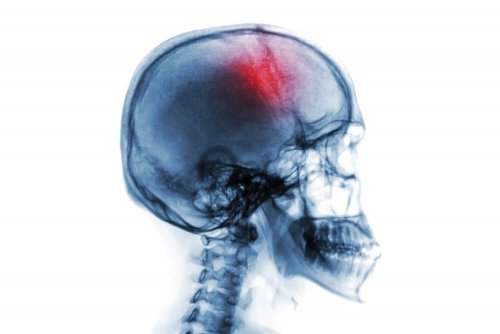

L’apoplessia, nota anche come colpo apoplettico, è una patologia caratterizzata da un’improvvisa emorragia o riduzione del flusso sanguigno nel cervello. Quando il sangue non raggiunge in maniera corretta il cervello, si produce la morte del tessuto cerebrale. Ciò si traduce in un deficit neurologico che può causare disabilità e persino la morte.

In realtà, il termine apoplessia si riferisce semplicemente al sanguinamento o all’interruzione del flusso sanguigno in qualsiasi organo. In tal senso, esistono diverse apoplessie a seconda dell’organo colpito. Tuttavia, quando la parola viene utilizzata da sola, in genere ci si riferisce a un accidente cerebrovascolare. L’incidenza di apoplessia è elevata, soprattutto negli anziani. Per tale ragione, è importante conoscere i sintomi e i fattori di rischio collegati.